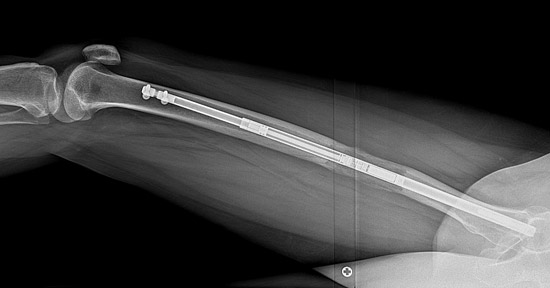

How does the lengthening device work?

The lengthening device utilized most often at HSS contains two metal rods, one inside the other, and a small magnet and gears. An external magnet used by the patient connects to the internal magnet within the rod, which twists the gears and causes the two rods to separate. This "distraction" phase happens in very small increments, controlled by the surgeon and the patient, so that healing of the new bone growth ("consolidation") occurs during the lengthening.

Femurs at end of distraction.